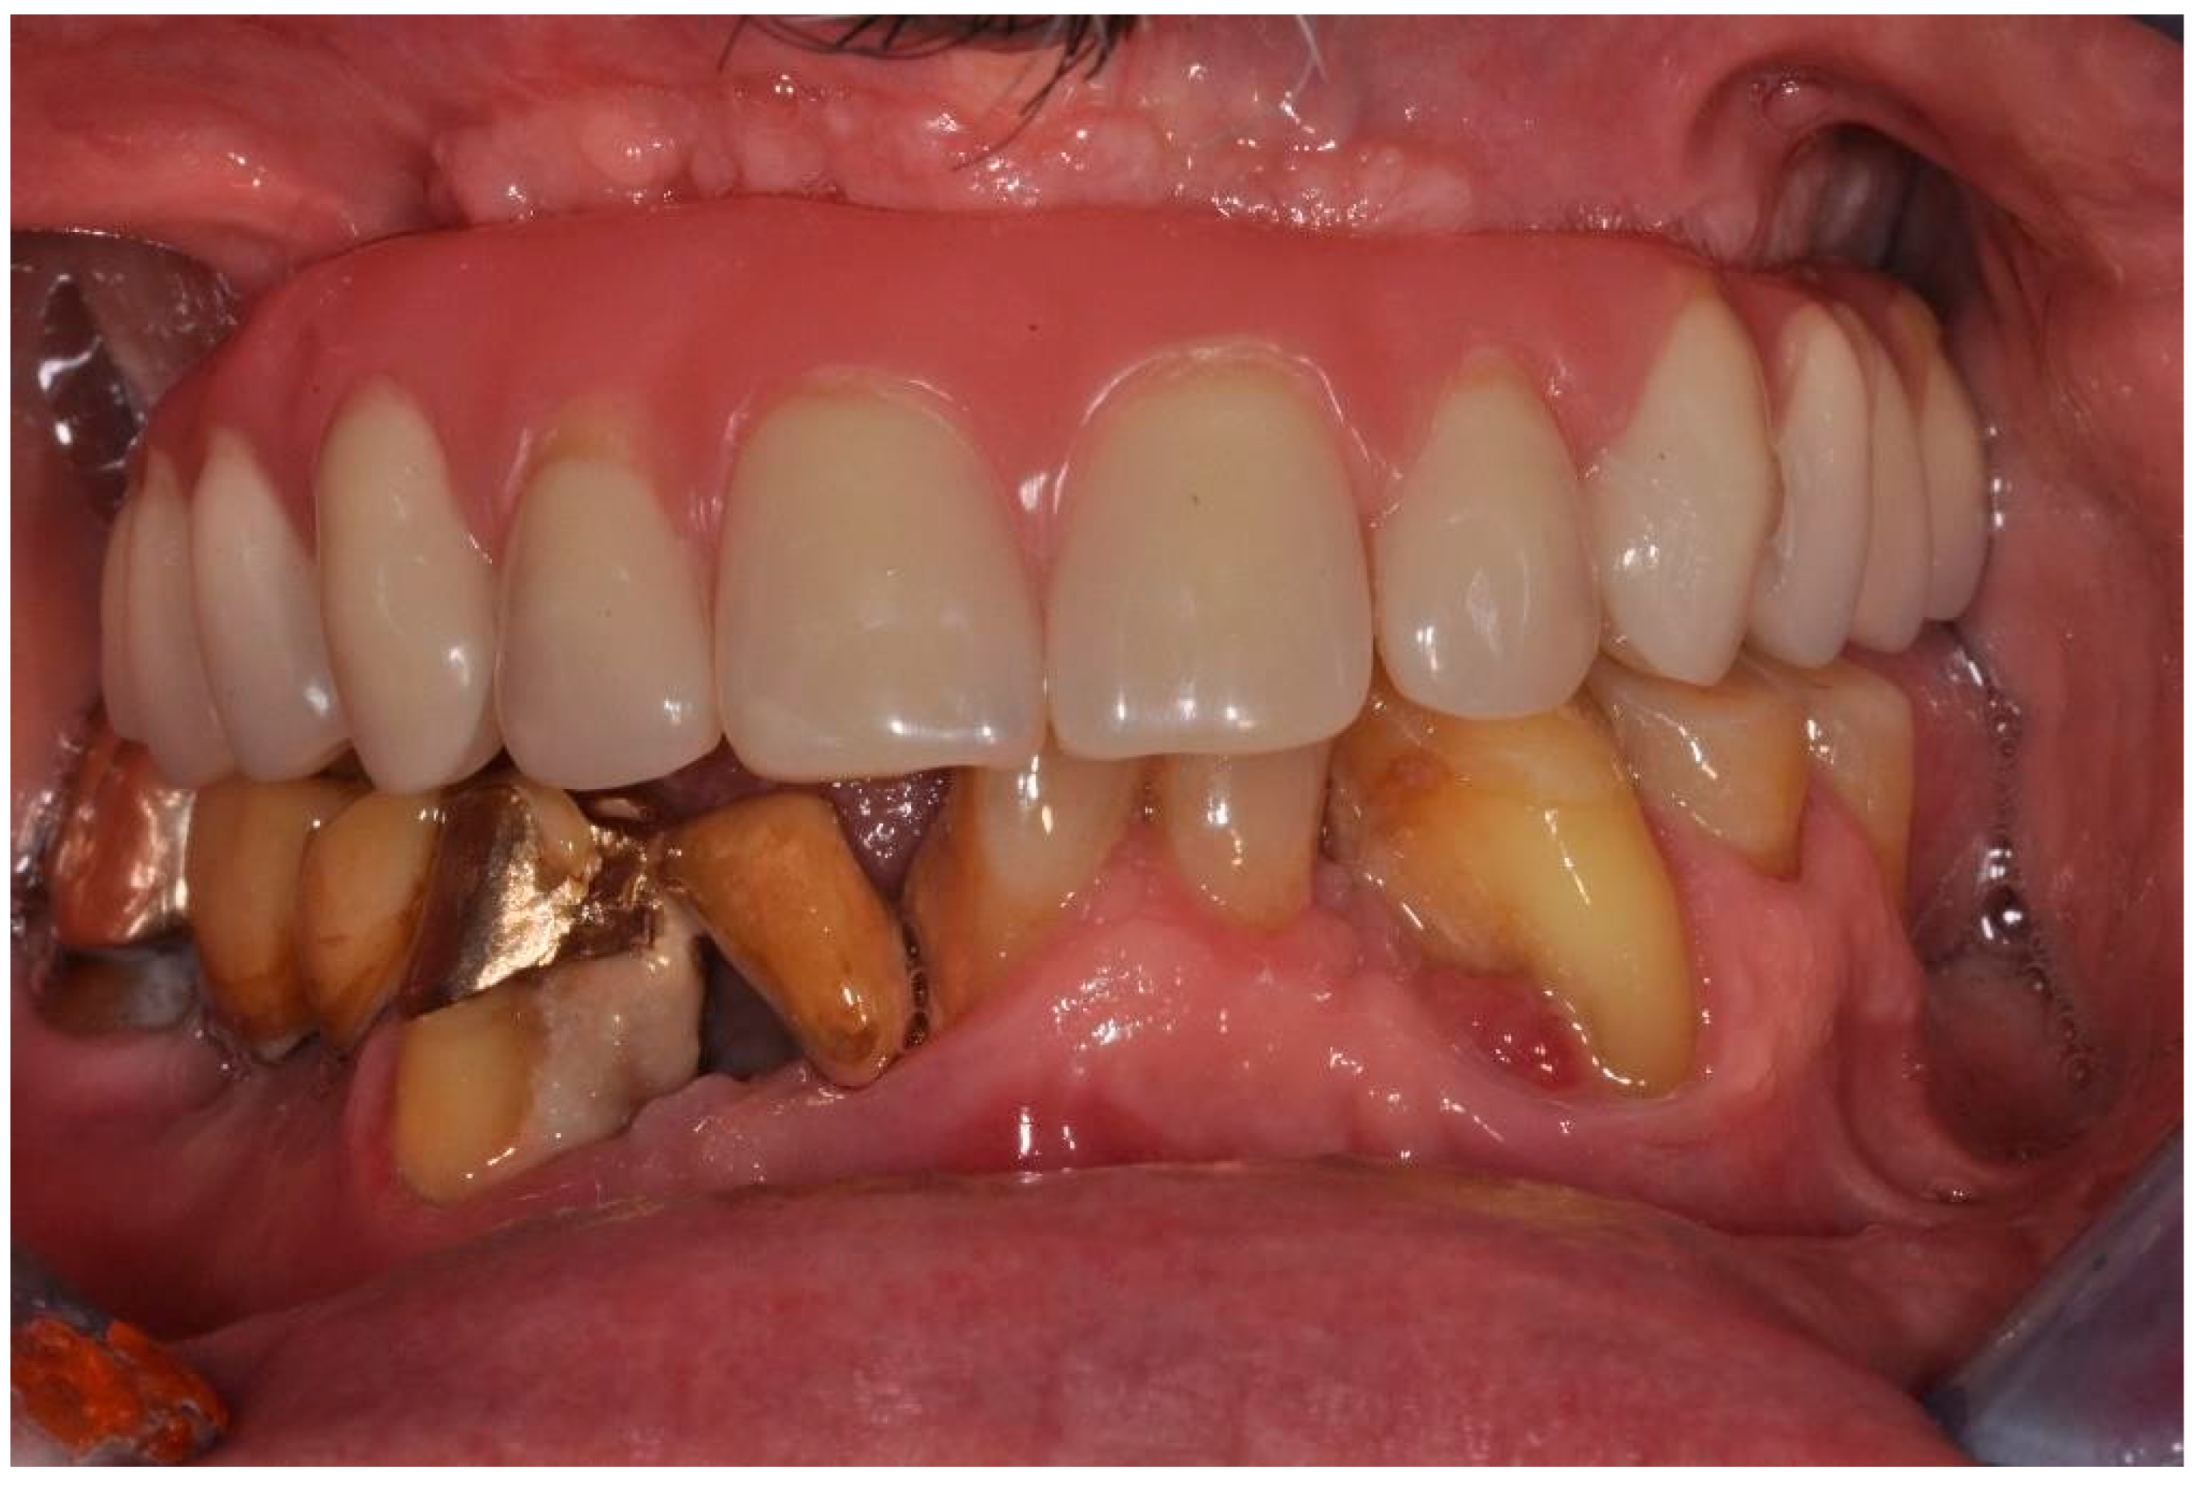

| Flanagan D. et al. [23] | J Oral Implantol | 2015 | clinical and radiographic: full-mouth radiographic series, panoramic and a bimaxillary cone beam computerized scan and mounted study casts | -One patient | Subject of 34 yo male; severely carious teeth and associated chronic abscesses (kidney transplant delayed) Comorbidities: IgA nephropathy, tabagism, hypertension and secondary hyperparathyroidism. Hemodialysis three times weekly. Ph. Therapy: Nephrocaps vitamin (B) supplement, amlodepine, besylate, cinacalcet, metoprolol, paroxetine. Bilateral compound ulnar and radial fractures, 2 blood transfusions. | Successfully treated with dental implant-supported fixed prostheses: fixed bimaxillary porcelain fused to metal implant-supported complete dentures |

| Hernández G. et al. [26] | Clin Oral Impl Res | 2019 | AI, MCI and TP reduction in mineral density of the cortical and trabecular bone in CRF patients and more severely in patients under haemodialysis compared to peritoneal dialysis | 1 IF in T | Mean follow-up of 116.8 months range from 84 to 192 months) | Renal transplant patients, are subjected pharmacological immunosuppression therapy |

| Flanagan D. et al. [23] | J Oral Implantol | 2015 | -Implant treatment for patients with IgA nephropathy (secondary hyperparathyroidism and osteodystrophy) may be successful. -Appropriate calcium therapy is important serum calcium to prevent inappropriate bone remodeling | 2 years | Long-term dialysis patient with end-stage renal disease (ESRD)also referred to as chronic kidney disease (CKD) due to IgA nephropathy complicated by severe secondary hyperparathyroidism and renal osteodystrophy | |